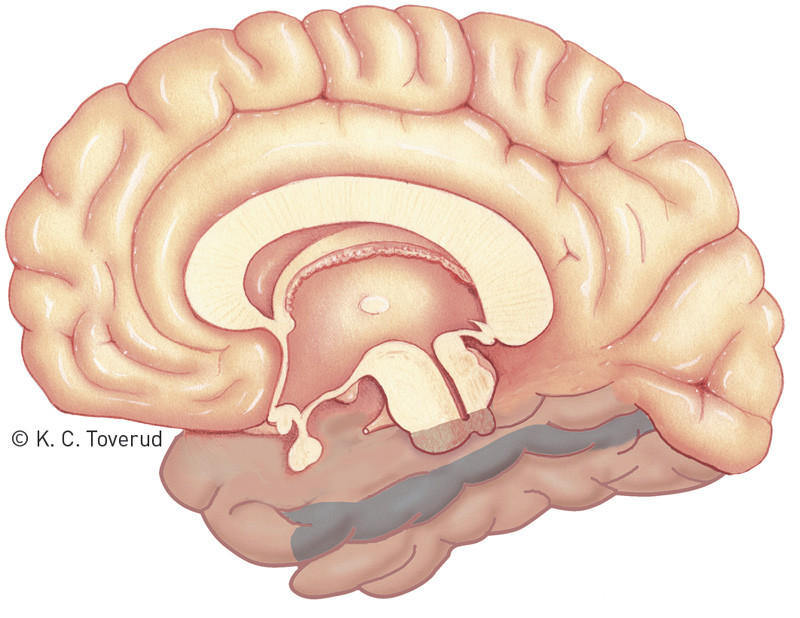

Our patient had clear cognitive symptoms that suggested involvement of one particular area of the brain. The most striking finding was her inability to recognise faces and familiar surroundings. Deficits in the brain’s ability to interpret visual stimuli can be divided into those that reflect disruption to the association fibres projecting from the occipital lobe to the parietal lobe («where» pathway deficits) and those that reflect disruption to the association fibres projecting to the temporal lobe («what» pathway deficits) (Fig. 2) (10, 11). The visual agnosias belong to the latter group. They are usually defined as an inability to recognise objects that is not due to sensory impairment or general intellectual impairment (i.e., «what» pathway deficits).

Figure 2  According to the two-streams hypothesis, the final visual image is the result of processing in two pathways. The…

Figure 2 According to the two-streams hypothesis, the final visual image is the result of processing in two pathways. The association fibres of the occipital lobe project via these pathways to the parietal lobe (arrow) and temporal lobe (arrow). The deficits in our patient suggested disruption of the occipitotemporal pathway

Figure 4  Medial view of the right hemisphere, with the fusiform gyrus of the temporal lobe marked in blue. Functional MRI…

Figure 4 Medial view of the right hemisphere, with the fusiform gyrus of the temporal lobe marked in blue. Functional MRI studies have implicated an area within the fusiform gyrus in face recognition, often referred to as the «fusiform face area» (FFA) (not marked on figure)